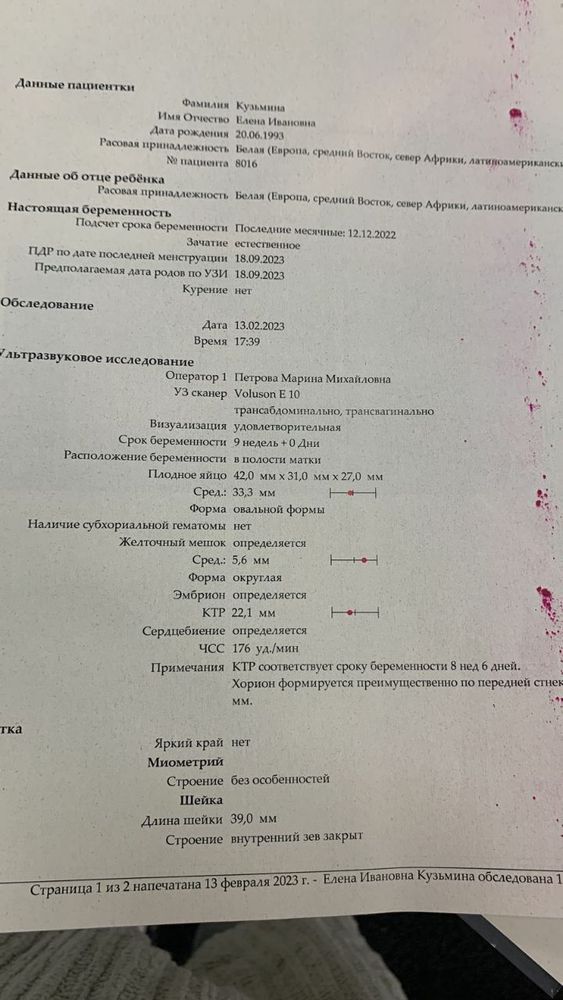

Вы уже спрашивали,в декабре зачатие было,в январе не могло быть,вам бы на 16 дпо не нашли пя 7 мм с жм,это как минимум 3 недели от зачатия было уже

Марина, Добрый День, извините но там не 7 мм, там написано 0,7 мм

Gennady Babansky, там опечатка 0,7 см или 7 мм,там же жм ещё есть,а оно внутри пя,как может быть пя 0,7 мм,а внутри жм 1,7 мм? Жм больше пя? Да и пя 0,7 мм на узи не разглядели бы 100%

Gennady Babansky, ну так здесь пя 7 мм,а не 0,7 мм,просто в протоколе стоит мм,а написали значения в сантиметрах

Gennady Babansky, у ва даже на самом узи написано, что ПЯ 0,75 СМ, и ЖМ 0,17СМ, а в описании узи опечатка.

Gennady Babansky, ну во первых на узи от 16 января у вас нет никакого ктр, вы путаете, видно только ПЯ(плодное яйцо) и ЖМ(желточный мешочек), а КТР это копчико теменной размер плода, это размер вашего эмбриона, но на том узи еще маленький срок и эмбриончика не видно, ПЯ еще совсем маленькое, в таком случае срок определяется по размеру ПЯ, это как раз где-то 5 нед и 3 дня акушерских. Считают только акушерский срок, эмбриональный всегда на 2 недели меньше акушерского, он считается от даты зачатия, а акушерский от даты последних месячных, всегда все считают по акушерскому сроку, и ребенок по узи должен соответствовать акушерскому сроку. А приложения все и размер КТР в приложении вообще не соответствует реальности, по их меркам дети аксилераты должны быть, такого не бывает, и вес и размер там в разы больше реальных, и тем более все детки разные и растут по разному. Плюс на разных узи ребенок может оставать и опережать срок, это норма и это не значит, что дата зачатия меняется, детки растут скачками. Не забивайте вы голову, не может быть 1 января дата зачатия, хоть там и небольшая разница в числах всего неделя, НО если бы у нее зачатие было 1 января, то 16 января на узи было бы пусто, не увидели бы даже ПЯ, не то что ЖМ (он появляется позже, чем ПЯ)

Gennady Babansky, это узи также подтверждает, что менструация была 12.12, срок по ней 9 недель, ребеночек не отстает в развитии от акушерского срока, это прекрасно. КТР также соответствует сроку беременности, тут уже только отталкиваться от срока беременности, тут уже глупо судить о дате зачатия. Но все же это лишний раз подтверждает, что все правильно, зачатие было 25-26 декабря. У вашей девушки явно цикл был всегда 28 дней и овуляция значит происходит на 14 день цикла, и сроки этому соответствуют. А это значит, что овуляция у нее как раз была если месячные 12 декабря, то 26 декабря овуляция, а после овуляции невозможно забеременеть. 1 января это уже 20 день цикла и овуляция уже прошла раннее

Марина, Здравствуйте ПЯ 7,5 мм обнаружили с помощью трансвагинального узи, есть ли разница в узи смотреть через живот и так?

Gennady Babansky, здравствуйте,на ранних сроках трансвагинально и смотрят,по животу могут и не увидеть такое крохотное плодное яйцо

Марина, Вот пишут что типа 7 дней до имплантации проходит и потом пя растёт 1 мм в день то есть 7мм это 7 дней получается? Получается 14 дней ну плюс, минус 15 грубо говоря, и выходит что на 16 января прошло столько времени, так может быть?

Gennady Babansky, расти оно начинает после 14 дня от зачатия только и пя 7 мм соответствует 3+ недель от зачатия,две беременности отслеживала овуляцию,в одну на 22 дпо т.е 3,1 от зачатия пя 7 мм было,в другую на 22 дпо пя 8 мм

Марина, Я просто не понимаю одного, я пересмотрел кучу видео и много прочитал статей, от 5 до 10 дней идёт процесс от зачатия до прикрепления, далее пя начинает увеличиваться по 1 мм в день на снимке оно 7,5 мм если допустим это 1 января, получается что к 7 или может 8 числу оно прекрепилос и как раз ещё за 7 дней выросло так и 16 Января увидели пя 7,5 мм, так сходиться всё просто

Gennady Babansky, не может быть пя 7 мм на 16 дпо,с таким размером пя хгч хгч 5000-8500 в среднем,на такое дпо даже с супер ранеей овуляцией и быстрым ростом хгч не будет такой уровень,для примера мой рост хгч, овуляция отслежена была

22 дпо УЗИ пя 8 мм,жм 1,6

Марина, Спасибо, получается что ну плюс, минус у всех, пя 7 мм где-то на 21,22 дпо

Gennady Babansky, да все верно,да и на собственном опыте двух беременностей на 22 дпо в одну 7 мм было,там хгч помедленнее рос,в другую 8 мм,там рост стремительный был

Gennady Babansky, в вашем случае овуляция нормальная была,не поздняя,да и дальше ведь УЗИ делали,там должен был акушерский срок с месячными совпадать

Gennady Babansky, ну вот все совпадает,значит овуляция была на 14 д.ц, соответственно 25 декабря зачатие было,с поздней овуляцией сроки не совпадают,на столько на сколько была поздняя овуляция

Елена Ивановна , ктр соответствует,а остальное оно скачками растет и может и больше и меньше быть,у меня например у старшего окружность головы опережала вообще на 5+ недель,он и родился с большой головой как у трёхмесячного ребенка и после первого скрининга срок обогнял к концу беременности на 2 недели,но он просто крупный был,второй тоже обгонял срок и тоже крупный был,но пдр не меняли,так как крупный не равно зрелый

Елена Ивановна , да зачатие было 25 декабря это прям 1000%

Елена Ивановна , если б зачатие было 1 января,сроки бы не совпадали с УЗИ,по узи бы срок на неделю меньше был бы,т е там где 9 недель по месячным,по УЗИ бы ктр на 8 недель был,а у вас все по сроку,да и дальше все соответствует,да и тест 11 января 2-3 недели,минимальное значение при котором тест показывает 2-3 это от 120 и выше,до 120 -1-2 ещё показывает,на 10 дпо хгч даже с самой ранней имплатацией не дорастет до таких цифр,у меня с ранней имплатацией -27 всего было на 10 дпо,видела максимум 50 на такое дпо,в вашем случае вообще нет сомнения что зачатие было точно в декабре

Елена Ивановна , аппарат ставит акушерских срок на основе размера эмбриона до 14 недель,дальше уже другие параметры учитывают,но дальше уже по УЗИ может и больше быть и меньше,это индивидуальные особенности,не все же дети одинаковые рождаются,у кого-то крупный плод и будет по узи обгонять срок,у кого-то наооброт маленький и может отставать,а до первого скрининга плод развивается практически одинаково

Елена Ивановна , судя по полоскам там хгч уже в районе 500 был

Елена Ивановна , 9 января уже судя по тестам 15 дпо точно было,вот мои тесты хгч -475 и 15 дпо

Gennady Babansky, нет не больше,как раз соответствует сроку 3 недели от зачатия,у кого хгч медленнее растет может и 4-5 мм быть в 3 недели от зачатия

Вот есть ещё узи от 13 февраля

Вот есть ещё узи от 13 февраля